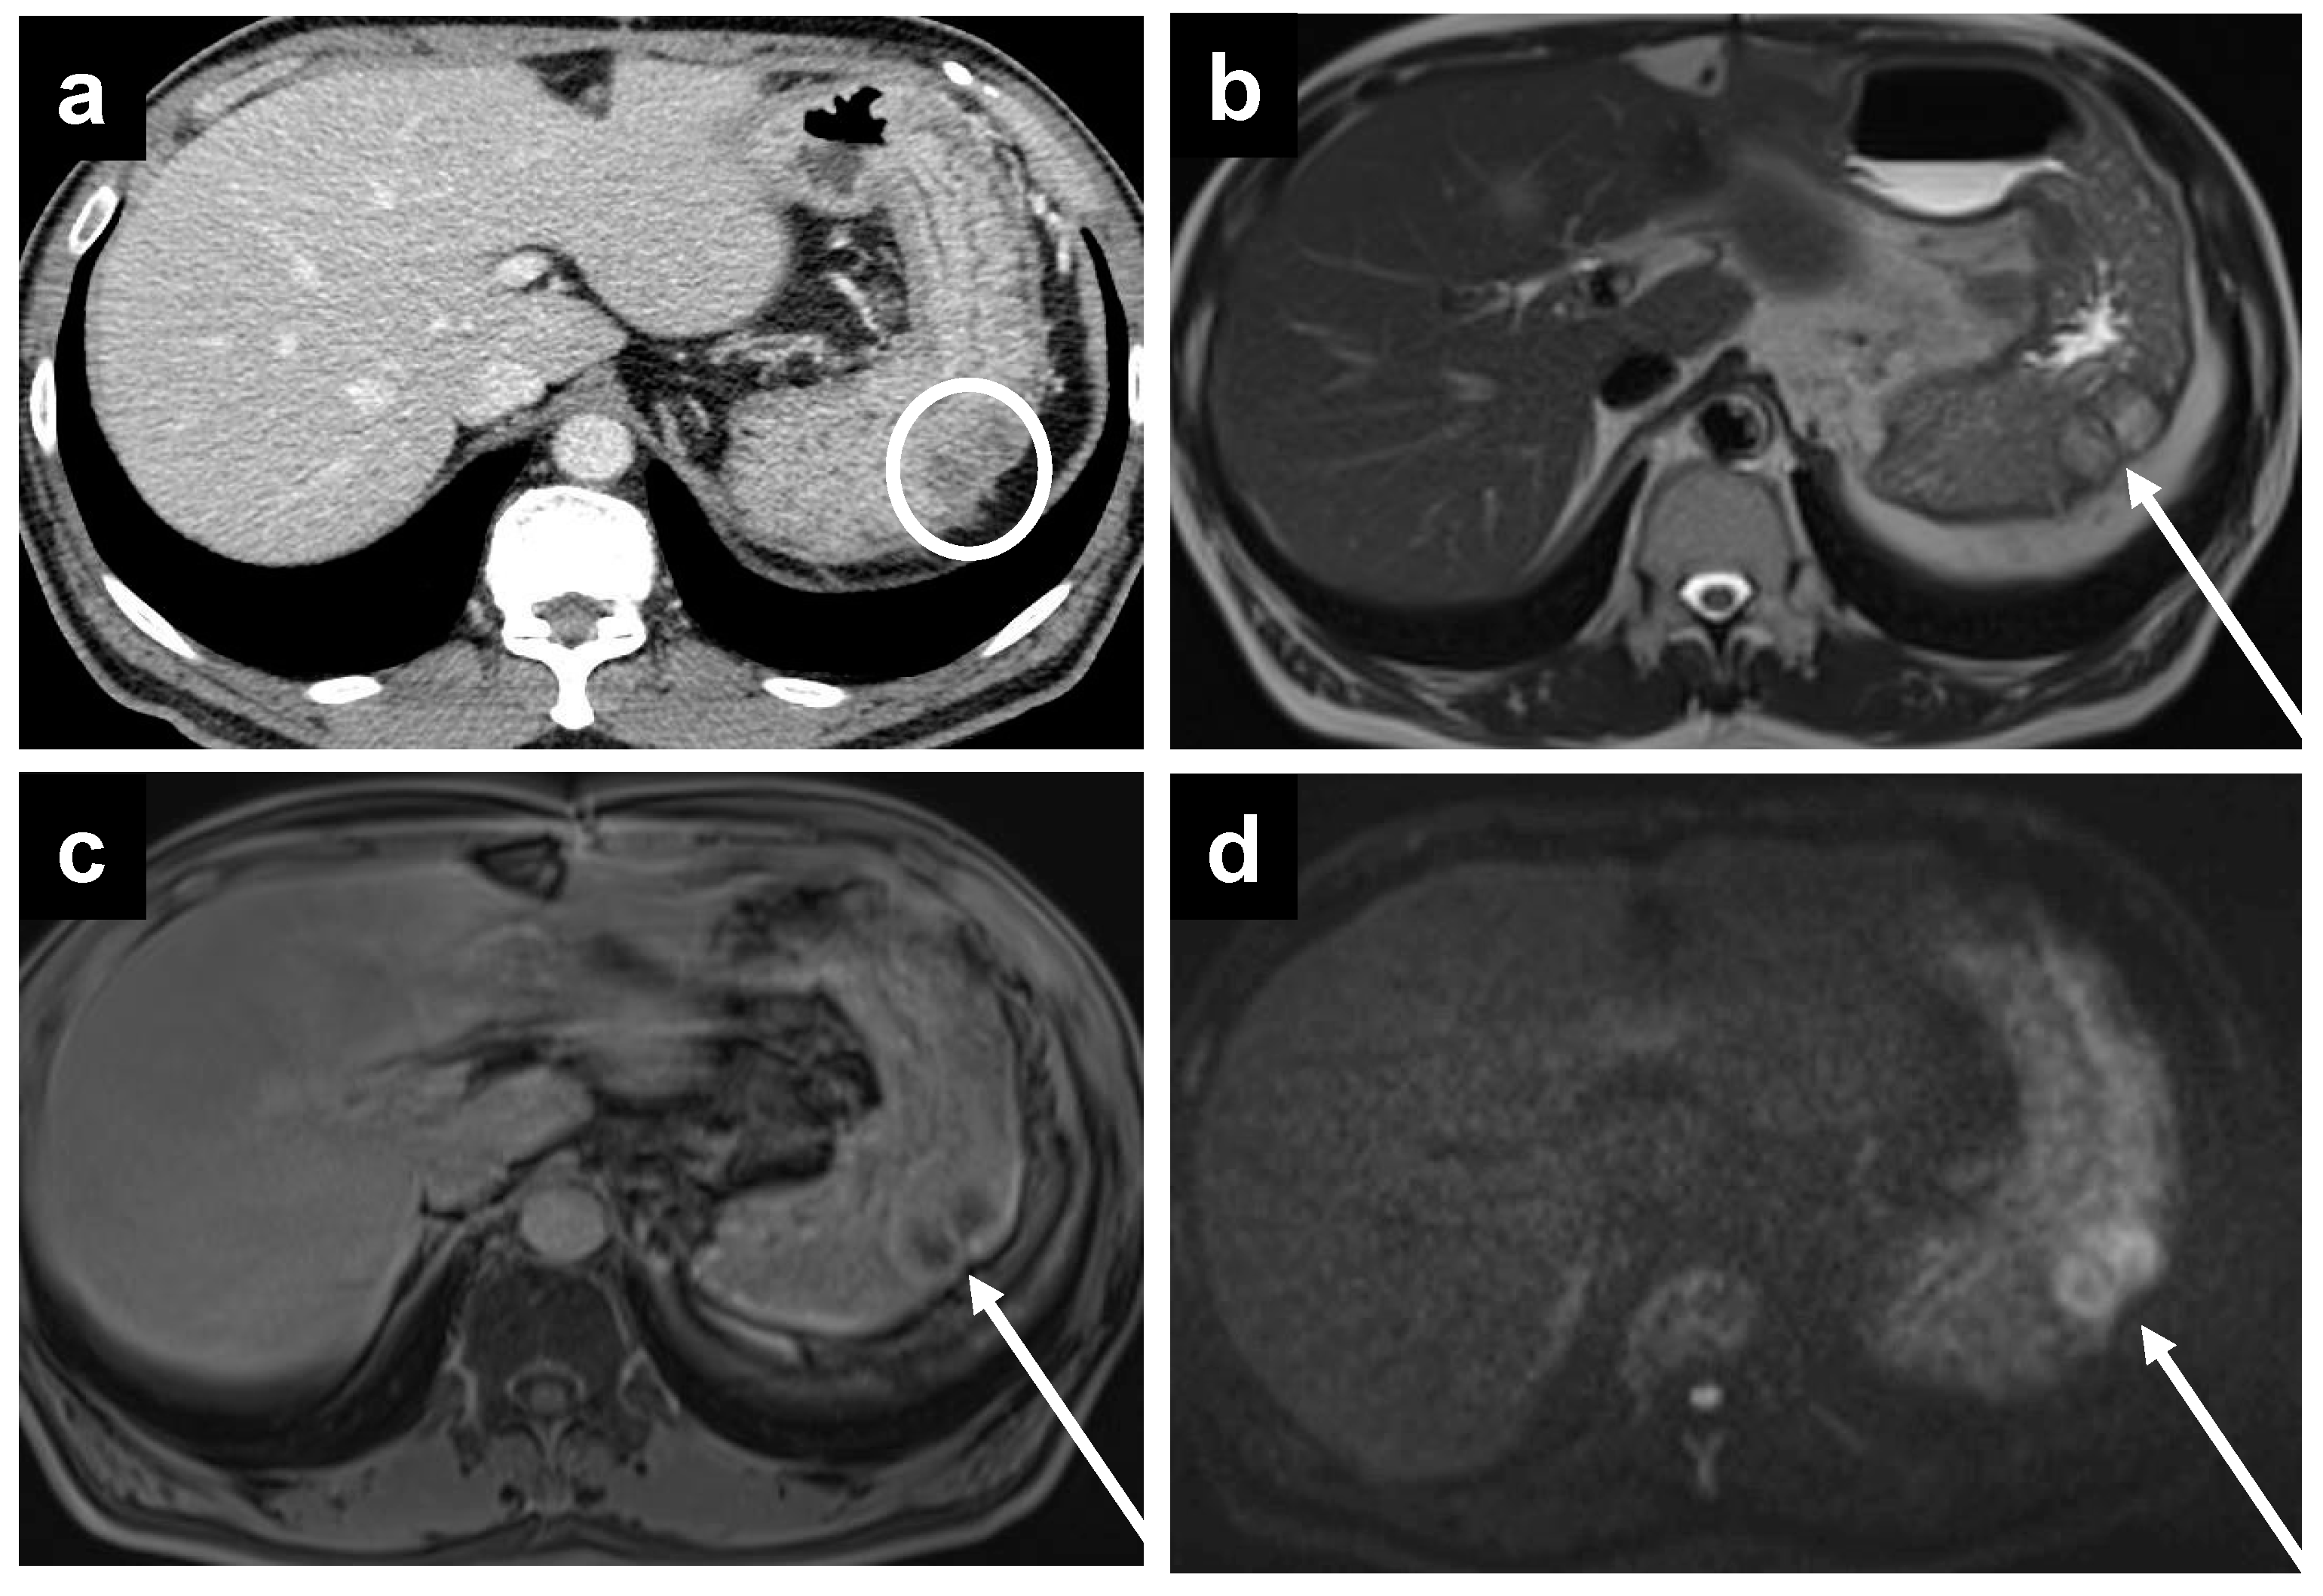

Figure 4.

A 55-year-old female with PMP. (a) CT reveals no significant abnormality, but MRI performed on the same day demonstrates a thin enhancing line surrounding the liver on the (b) portal venous phase, which becomes more apparent on the (c) delayed phase.